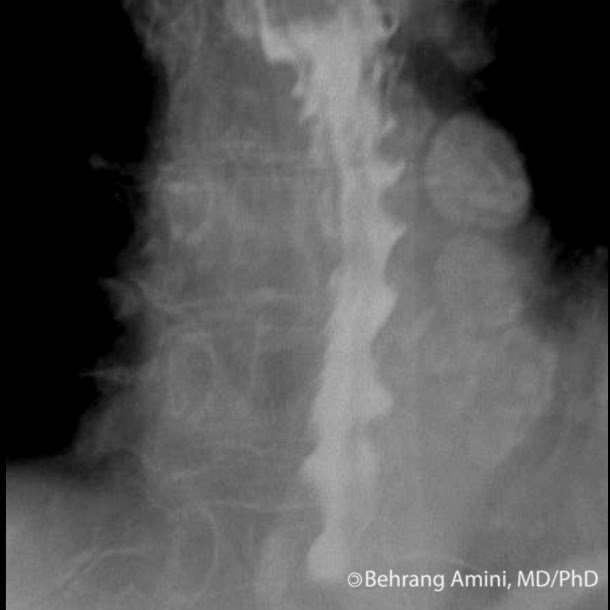

a Contrast upper gastrointestinal series showed a corkscrew sign of the Corkscrew Sign A corkscrew appearance of the duodenum and proximal jejunum (figure 1) was pathognomonic for midgut volvulus. Midgut volvulus is a complication of bowel malrotation usually seen in neonates and infants. This case report raises awareness on subtle but important conventional imaging findings that suggest the presence of an av. The corkscrew sign describes the spiral appearance of the distal duodenum. Corkscrew Sign.

Corkscrew Sign . The corkscrew sign describes the spiral appearance of the distal duodenum and proximal jejunum seen in midgut volvulus. The corkscrew sign (figure 1b) refers to the twisted configuration of the proximal small bowel loops seen on upper gastrointestinal (ugi) in. A corkscrew appearance of the duodenum and proximal jejunum (figure 1) was pathognomonic for midgut volvulus. Presentation is usually with proximal. This case report raises awareness on subtle but important conventional imaging findings that suggest the presence of an av. Findings suggestive of malrotation include a low djj, duodenal redundancy, and corkscrew appearance of djj [2, 26]. Midgut volvulus is a complication of bowel malrotation usually seen in neonates and infants. The twisted, vertically oriented configuration of the duodenum seen on an upper gastrointestinal (ugi) series (figs.

Midgut volvulus is a complication of bowel malrotation usually seen in neonates and infants. Findings suggestive of malrotation include a low djj, duodenal redundancy, and corkscrew appearance of djj [2, 26]. This case report raises awareness on subtle but important conventional imaging findings that suggest the presence of an av. The corkscrew sign describes the spiral appearance of the distal duodenum and proximal jejunum seen in midgut volvulus. A corkscrew appearance of the duodenum and proximal jejunum (figure 1) was pathognomonic for midgut volvulus. Presentation is usually with proximal. The twisted, vertically oriented configuration of the duodenum seen on an upper gastrointestinal (ugi) series (figs. The corkscrew sign (figure 1b) refers to the twisted configuration of the proximal small bowel loops seen on upper gastrointestinal (ugi) in.